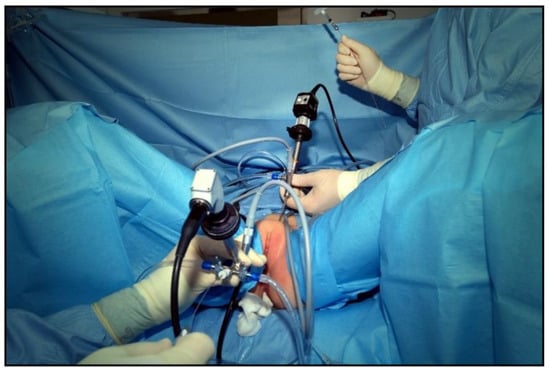

With the patient under general anesthesia in the lithotomy position, antegrade urethrocystoscopy was performed using a 9.5 Fr cystoscope (Figure 1). In parallel, percutaneous suprapubic bladder access introducing a second 9.5 Fr. cystoscope was accomplished. Four quadrant Dx/HA injections were performed, with the two surgeons guiding each other by parallel endoscopy to the optimal localization for injection (Figure 2, Figure 3 and Figure 4). In selected patients, the procedure was completed with transurethral intravesical Botox® injection. At the end of the procedure, a transurethral Foley catheter was placed and left in place for 10 days. Patients were discharged on the first day after surgery and they returned to the outpatient clinic for scheduled removal of the Foley catheter.

Figure 1.

9.5 Fr cystoscope with metal needle (2 sets needed).